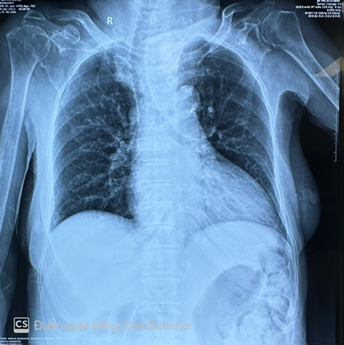

This case involves a 73-year-old woman who initially presented with weakness of lower extremities and dyspnea for two weeks duration. Her history diseases were hypertension, type 2 diabetes and lumbar spine osteoarthritis she had no significant cardiac family history with no history of sudden cardiac death. Physical examination was remarkable for a 3/6 crescendo systolic murmur heard best at the right upper sternal border. Electrocardiography showed sinus rhythm 95 bpm, left ventricular hypertrophy (figure 1). Chest xrays showed a large cardiac shadow (figure 2). Transthoracic echocardiography revealed a severe aortic valve stenosis, peak velocity of 4.10 m/s across the valve and peak gradient 67 mmhg (figure 3). The patient’s native aortic valve area was 0.6 cm2; moderate aortic valve regurgitation. Laboratory tests including routine full blood count showed moderate hypochromic microcytic anemia with hb: 7.4g/dl, renal and liver profiles were unremarkable. Abdominal ultrasound was normal.

Figure 2. Chest xrays showed a large cardiac shadow.